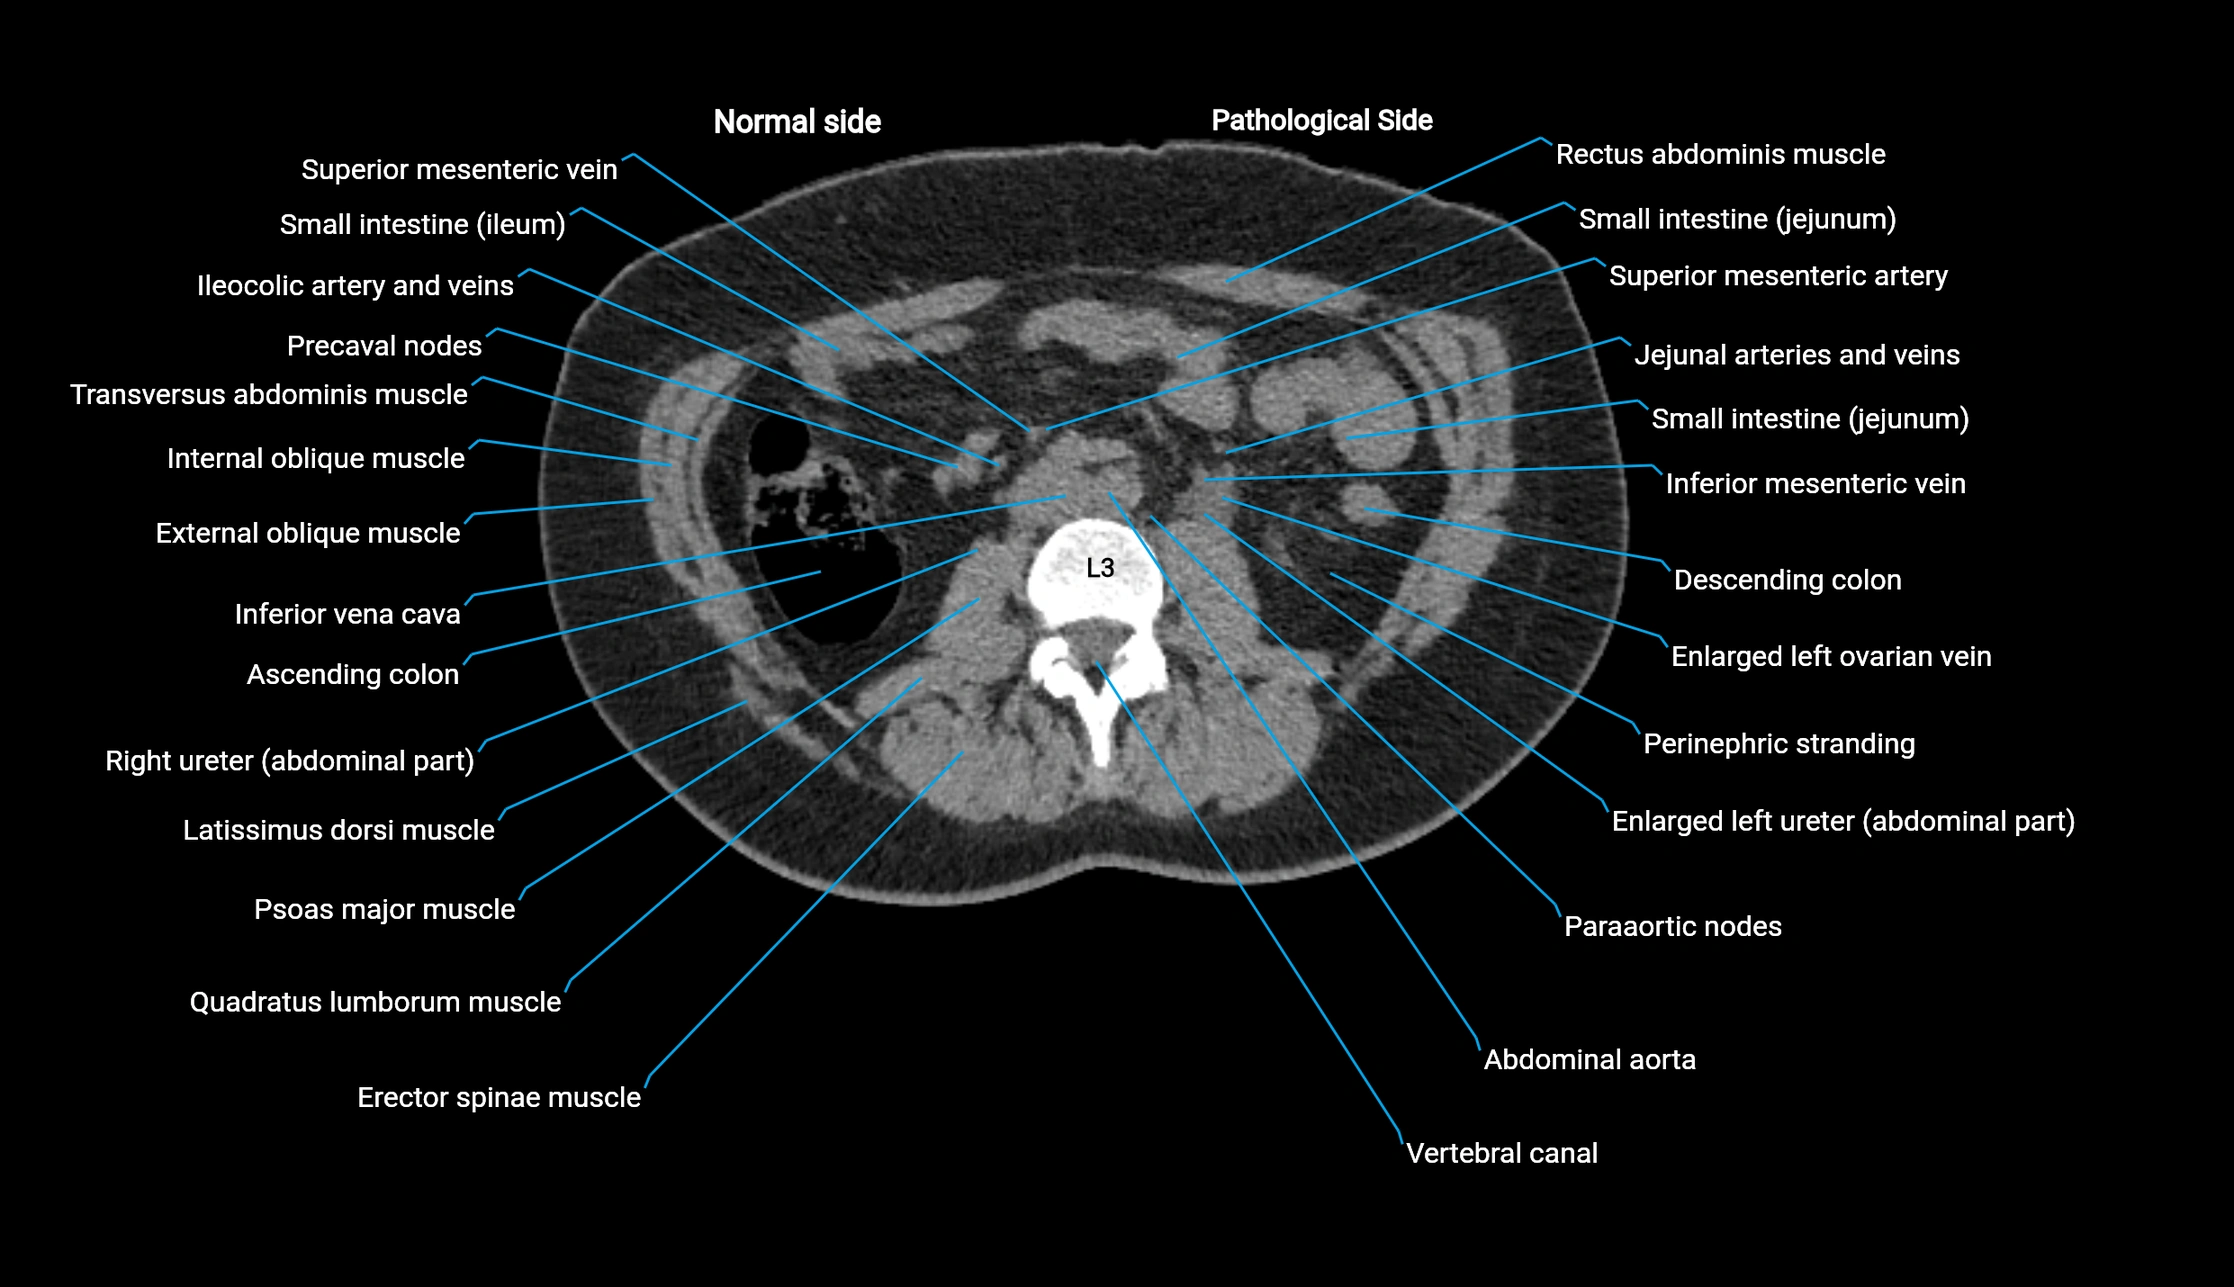

CT VRT 3D image

image